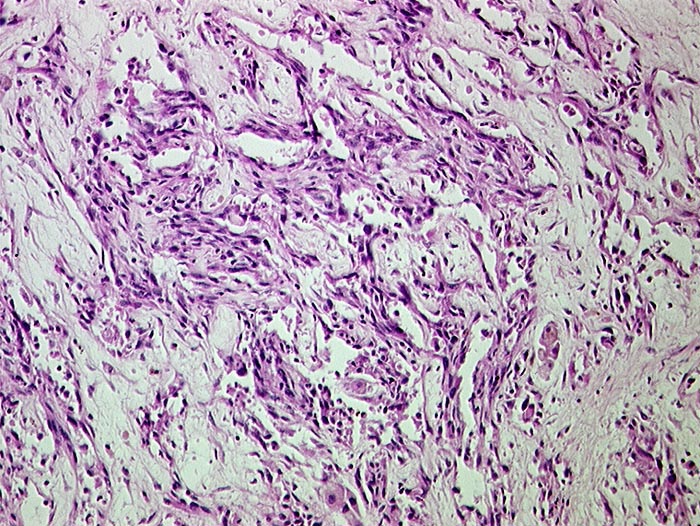

Angiosarkom der Leber

Pathologischer Befund